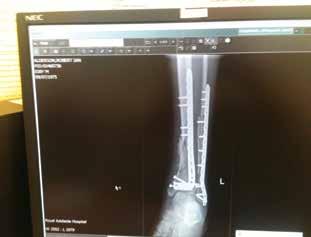

Above: in hospital after surgery in December 2013 wearing a bum bag which contained a balloon (inside a canister) for administering antibiotics; facing page, clockwise from top left: in the old RAH with a gauze dressing over the skin graft in November 2013; the wound in May 2015 after the internal metal work had failed; the wound after gracilis free flap surgery in November 2013; facing page below: Alderson’s left thigh from which surgeons took the skin graft.

Above: Alderson and wife Julie; facing page, top: X-rays which showed the internal reconstruction work in October 2013; below: in hospital the day after his amputation in October 2015.